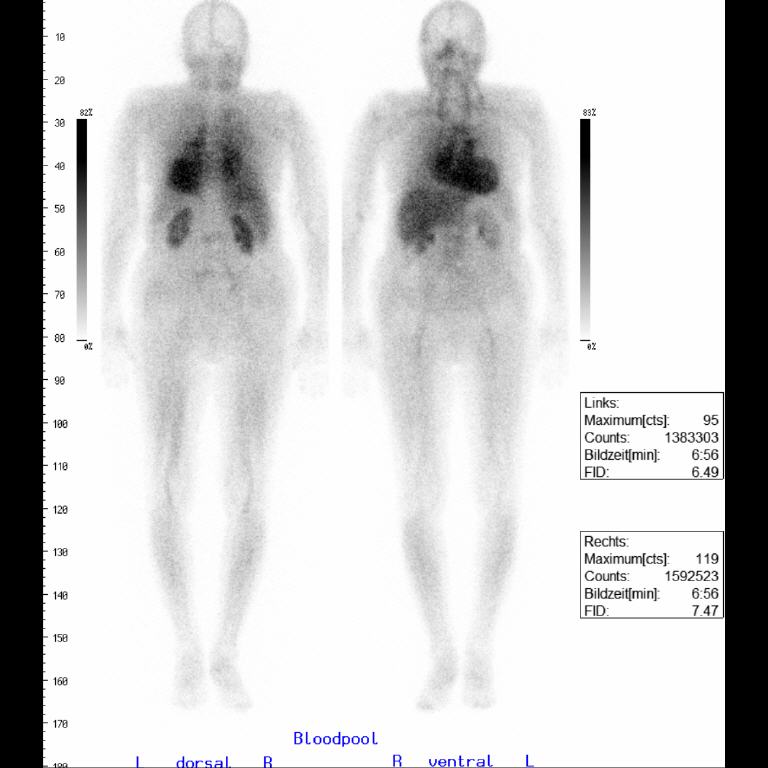

Eine häufige Form, welche besonders bei Männern älter als 65 Jahre auftritt, ist die Transthyretin - Amyloidose mit Kardiomyopathie (ATTR-CM). Typisch für diese Erkrankung ist, dass sich die für die Knochenszintigraphie verwendete Substanz auch im Herzmuskel anreichert. Die Methode kann die Erkrankung bereits in einer frühen Phase erkennen. Mit einer medikamentösen Therapie (Vyndaqel) kann das Voranschreiten der Erkrankung verzögert werden.

Das Bildbeispiel zeigt eine Mehrphasen - Skelettszintigraphie mit typisch vermehrter Herzdarstellung in der Mineralisationsphase.